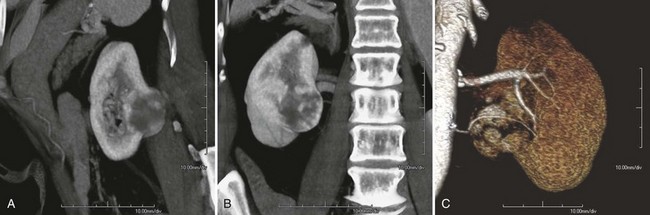

Before partial nephrectomy, evaluation of patients with renal cortical tumors should include imaging to identify locally extensive or metastatic disease. Preoperative imaging should also delineate relevant regional anatomy, intrarenal anatomy, and vasculature to minimize blood loss and damage to adjacent renal parenchyma. Invasive renal arteriography has largely been replaced by noninvasive 3D CT angiography, which offers excellent anatomic detail. 3D CT integrates information from arteriography, venography, excretory urography, and conventional two-dimensional CT into a single imaging modality (Fig. 54–130). In addition to tumor staging, 3D reconstructions of contrast-enhanced CT angiograms, MR images, or MR venograms are useful for planning site and extent of planned resection and to determine proximity to the renal hilum, intrarenal vasculature, and collecting system (Fig. 54–131). 3D CT accurately demonstrates involvement of the collecting system by tumor (Derweesh et al, 2003).

Figure 54–131 A, Contrast-enhanced CT scan demonstrating right renal mass. B, Three-dimensional reconstruction demonstrates a large intrarenal component to the mass. C, Arterial reconstruction shows lower pole renal artery in close proximity to the renal mass.